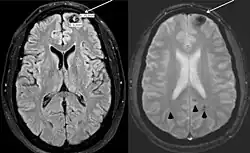

- ^ a b c Lizarraga, Karlo J; De Salles, Antonio AF (20 September 2011). "Multiple cavernous malformations presenting in a patient with Poland syndrome: A case report". Journal of Medical Case Reports. 5 (1): 469. doi:10.1186/1752-1947-5-469. PMC 3195104. PMID 21933407.